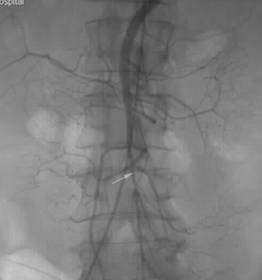

5.血管造影診斷本病的最可靠方法,對疑有本病者行主動脈造影,選擇性腹腔動脈、腸系膜上動脈及腸系膜下動脈造影術,確定血管狹窄閉塞的性質,部位、程度和範圍以及側支循環的建立,應拍側位和前後位片,可顯示明顯的動脈粥樣硬化症及一些血流動力學的改變,在主動脈根部1~2cm內常見動脈硬化病變,常有腸系膜2~3支動脈狹窄或完全閉塞,狹窄程度超過50%,有向腹主動脈的血液反流,同時伴有粗大蜿蜒迂曲的側支供血動脈,有時僅看到1~2主支狹窄但無粗大蜿蜒迂曲的側支血管,仍不能去確定診斷,臨床上血管病變與症狀並非一致,75%的人可有腸系膜動脈硬化的造影表現,值得注意的是,無症狀的老年人在腸系膜血管造影時10%~20%有明顯病變。

3.介入性放射學近年來介入性放射學的開展促進了慢性腸系膜缺血性疾病非手術治療的發展,開闢了新途徑,氣囊血管成形術是經皮股動脈穿刺後在腹腔動脈、腸系膜上動脈狹窄處進行導管氣囊擴張。另外,在上述主要動脈狹窄處放置鈦合金支架,可取得使血流通暢,改善缺血的同樣效果,適用於體弱難以承受手術者,有時可取代旁路移植或動脈內膜剝脫術。